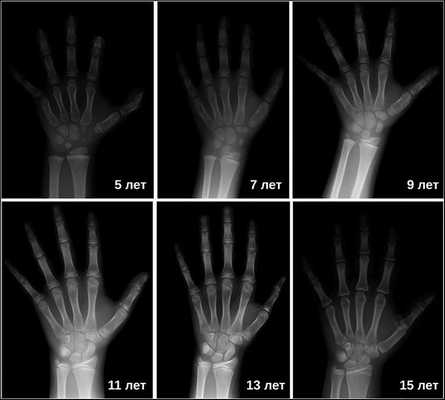

Затем врачи определяют костный возраст. Сделать это можно с помощью рентгена или УЗИ запястья. В норме костный возраст может отставать или опережать паспортный на два года.

Основной симптом — отставание в темпах линейного роста [2] . Такие дети вырастают менее чем на 4 см в год. Нарушение динамики роста будет заметно уже в первые месяцы жизни ребёнка. Если повреждение гипоталамуса или гипофиза возникло в более позднем возрасте, то отставание в росте будет отмечаться позднее. Также для детей с гипофизарным нанизмом характерно отставание костного (биологического) возраста от паспортного (фактического) более чем на 2-3 года.